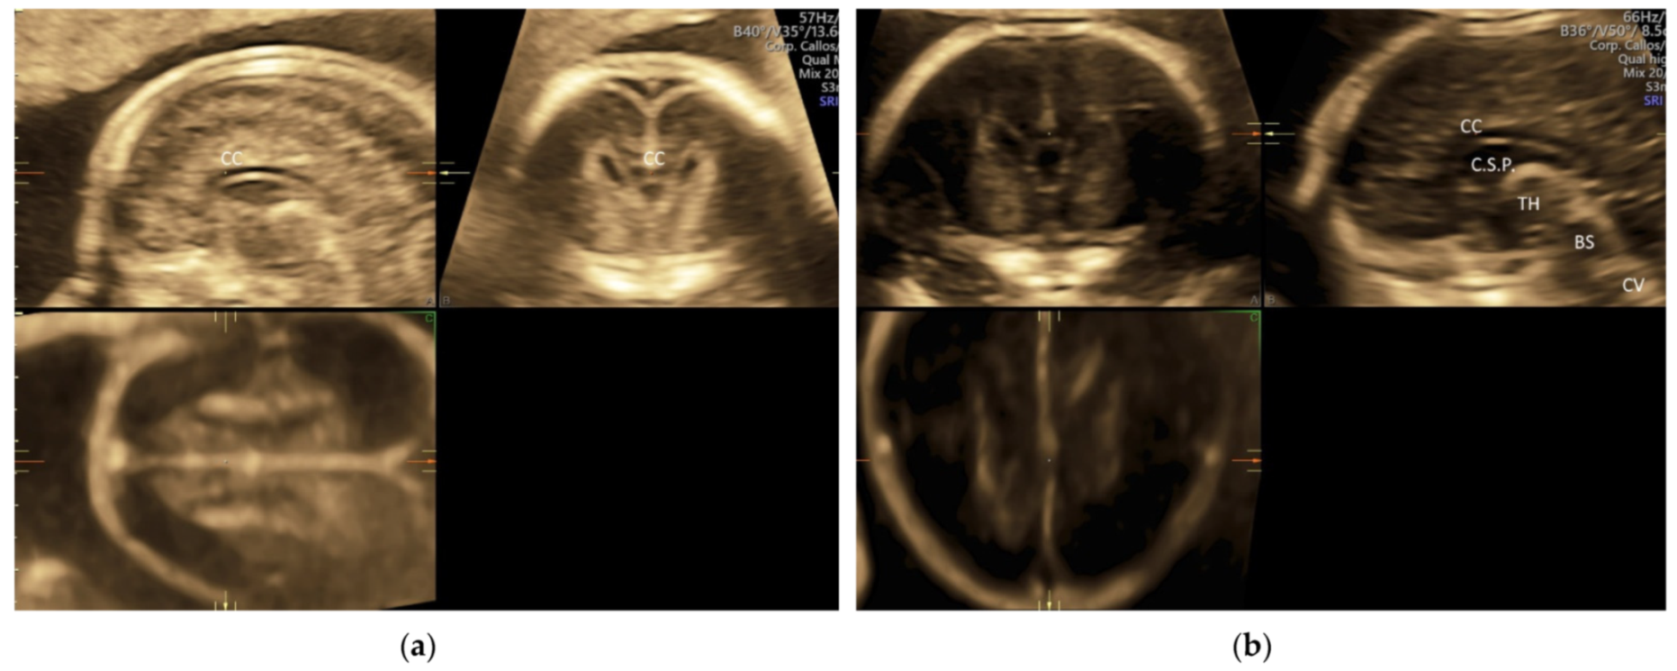

5.1. 3D Neurosonography

In targeted neurosonography, a systematic assessment of the fetal brain is required. Although this assessment can be performed by a 2D ultrasound examination, a perfect midsagittal view may not be achieved at all times, thus affecting a proper assessment. ISUOG recommends using 3D ultrasound examination that can provide images of enhanced resolution by displaying thicker ‘slices’ of the brain and thus increasing the signal-to-background noise ratio on all three planes. In addition, multiplanar imaging correlation allows the display of perfectly aligned views on the three orthogonal planes [5]. To avoid shallowing by adjacent skull bones, it is important to acquire a 3D volume in a mid-sagittal plane through the sagittal suture. If the focus is on the anterior complex, the volume will be obtained from the anterior fontanelle or the anterior part of the sagittal suture [5] (Figure 7a). If the focus is on the posterior fossa and cerebellar vermis, the volume will be obtained from the posterior fontanelle or the posterior part of the sagittal suture with the ultrasound beam being almost perpendicular to the tentorium [47] (Figure 7b). A transvaginal and transabdominal approach is used when the fetal presentation is vertex and breech, respectively. Then, the midlines structures including corpus callosum, brain stem, and cerebellar vermis can be examined by multiplanar and multi-slice analysis [43,48,49]. An accurate measurement of corpus callosum and cerebellar vermis can be achieved.

Figure 7.

Three-dimensional ultrasonography of fetal brain at 20 weeks’ gestation: (a) multiplanar analysis after a volume acquisition with corpus callosum mode through the anterior part of the sagittal suture showing corpus callosum (CC), and (b) multiplanar analysis after a volume acquisition through the posterior fontanelle showing corpus callosum (CC), cavum septi pellucidi (C.S.P.), thalamus (TH), brainstem (BS), and cerebellar vermis (CV).